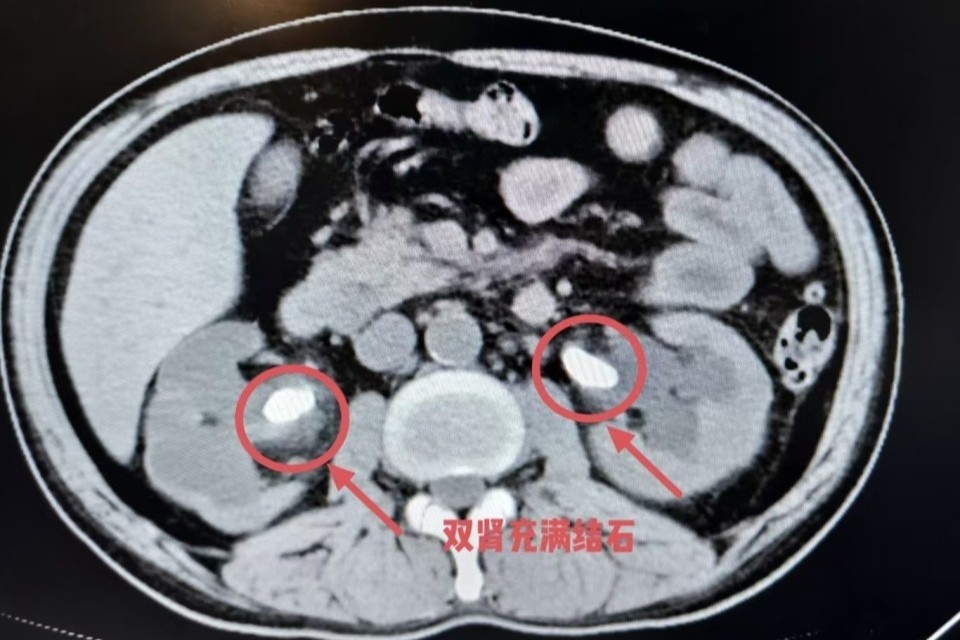

Truy tìm nguyên nhân khiến chức năng thận suy giảm nghiêm trọng, các bác sĩ tiến hành chụp CT và nhiều xét nghiệm chuyên sâu. Kết quả cho thấy trong cả hai quả thận của ông Ngô tồn tại sỏi kích thước khoảng 2 cm, nằm ở vị trí nối giữa thận và niệu quản.

Những viên sỏi này gây tắc nghẽn dòng nước tiểu trong thời gian dài nhưng gần như không gây đau. Thận bị ứ nước kéo dài, dần teo nhỏ và mất chức năng mà người bệnh không hay biết. Ông Ngô được chẩn đoán ứ nước hai thận do sỏi niệu quản, teo thận và suy thận cấp, sau đó được chuyển thẳng về khoa Tiết niệu để phẫu thuật.

Sỏi thận được tìm thấy trong cơ thể người đàn ông. Ảnh: QQ News.